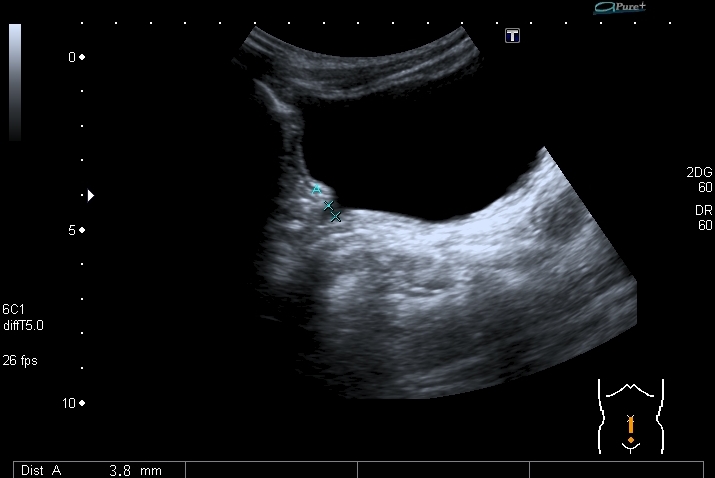

Мальчик 10 лет, госпитализирован впервые в связи с выявленными в ЦРБ изменениями на УЗИ. В анализах мочи - протеинурия, лейкоцитурия. В крови - уремия. В трёхлетнем возрасте - боли в спине, лечил нарушение осанки.

На УЗИ - следующая картина:

Почки:

Определяется небольшое расширение лоханок обеих почек, стенки их гиперэхогенные, утолщены.

Меня больше всего заинтересовало тканевое образование в нижнем полюсе левой почки - гиперэхогенное, многоузловое. Есть мысли про причину такого состояния почек, но пока хочу выслушать мнения коллег. Буду очень благодарен за отзывы.